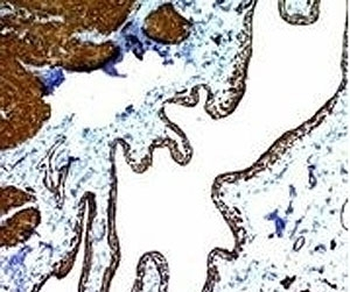

Immunofluorescent staining of fixed human HeLa cells with Smooth Muscle Actin antibody (clone SPM332, green) and NucSpot nuclear stain (red).

IHC: Formalin-fixed, paraffin-embedded Leiomyosarcoma stained with Smooth Muscle Actin antibody (clone SPM332).